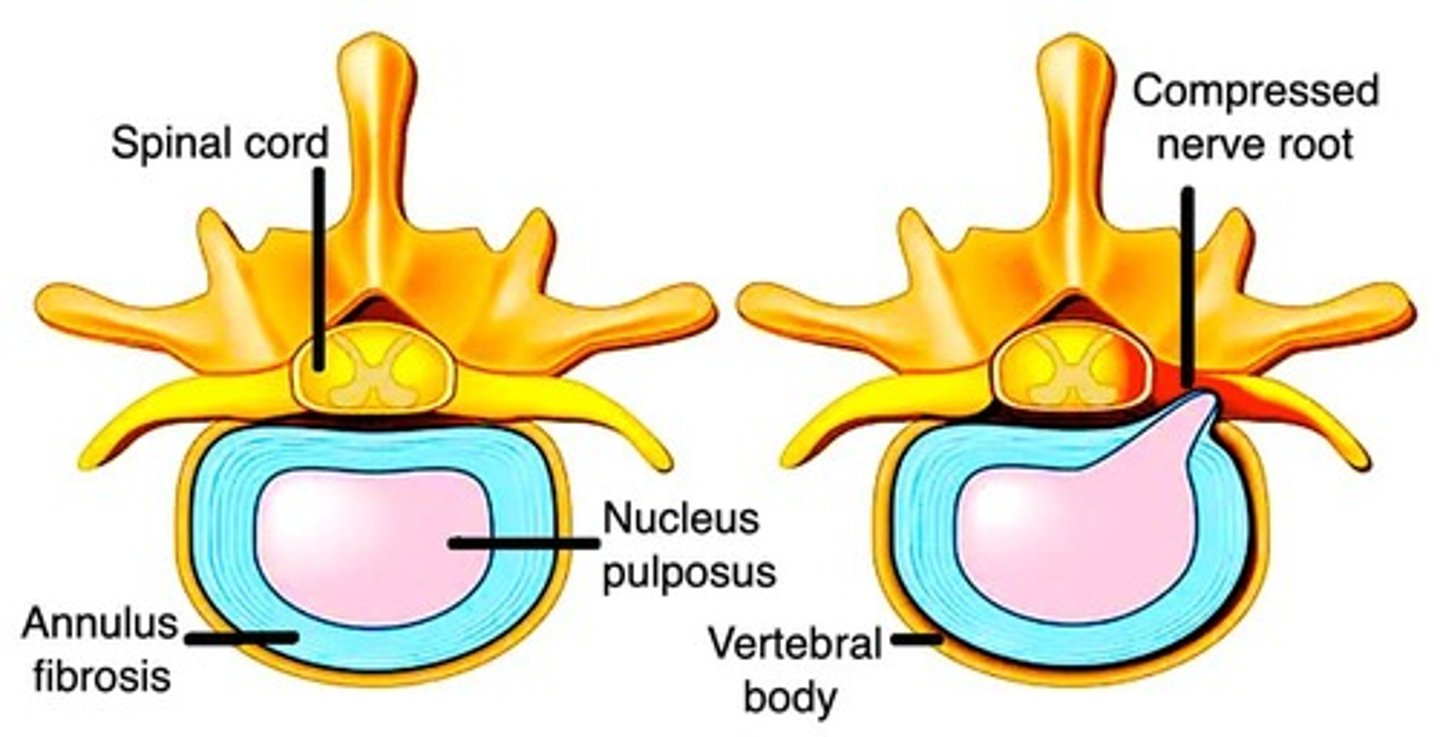

Carotid stenosis

Occurs from HTN, where an atheromatous plaque has launched off.